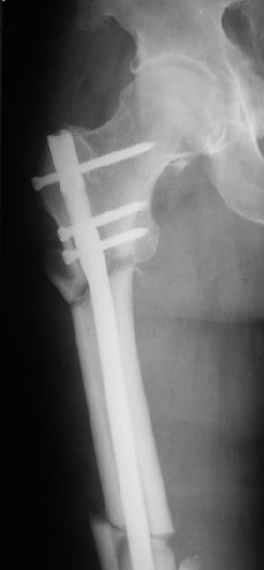

При межвертельных переломах с цефаломедуллярными гвоздями бывает, что проксимальый винт проходит или черед периферический отломок, или прямо над ним. И если остался диастаз, то этот винт при осевой нагрузке не дает сблизиться отломкам. Пример такого остеосинтеза в застарелом случае в приложении.

В качестве предупреждающей меры можно долотом разрушить латеральную стенку дистального отломка под винтом.

В частности, на проксимальном конце сделано еще одно дополнительное статическое отверстие. Можно ввести в проксимальном отделе 4 винта, из них 3 статические (2 в круглые отверстия и 1 по нижнему краю овального). Картинки в приложении. На дистальном конце стержня тоже кое-что улучшено. Спрашивайте в аптеках, как говорится. Выпускается предприятием "ЦИТО" (Москва), то есть это малобюджетное решение.

Конечно, мы не синтезируем остеопорозые вертельные переломы согласно прилагаемому примеру, винты 6 мм вырежутся. Но у более молодых при хорошем качестве кости такие или подобные гвозди с поперечным расположением винтов вполне применимы для меж- и подвертельных переломов.

Женя, эта картинка показывает не оптимальное лечение вертельных переломов в моем представлении, а особенности дизайна упомяутого фиксатора.

В частности, его возможности при фиксации переломов проксимального отдела бедра - в сравнении с другими, имеюшими лишь по одному статическому и динамическому отверстию и с кондуктором для введения 2 винтов.

Это было года 2,5 назад, мы тогда еще уточняли возможности шинирования с угловой стабильностью гвоздем с поперечным расположением винтов при переломах проксимального отдела бедра. Пациенту не пришлось приобретать намного более дорогой рекон или проксимальный гвоздь. В приложении еще несколько примеров применения того гвоздя при высоких переломах бедра, в том числе с более латеральной точкой входа. Гвоздь изгибаем для этого.